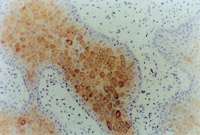

ԭλÇÐÈ¡´´Ãæ×éÖ¯²¡ÀíÇÐÆ¬²é³­£¬¼û»µËÀÉÏÆ¤×éÖ¯¼äÓдóÁ¿¿ÅÁ£Ñù×éÖ¯£¬ÐÂÉúÉÏÆ¤Ï¸°ûºÍ½ºÔ­ÏËά×éÖ¯³ÊÍÅÑùÔöÉú£¬²¢¿É¼ûµ½µäÐ͵ÄÀàËÆÓÚÌ¥¶ùƤ·ô½á¹¹µÄƤ·ôÅßÌ¥»ù(embryonic base,EB)(ͼ5-3-4a,5-3-4b)¡£MEBTÒ½ÖÎ10Ììºó£¬ÔÚ´´Ãæ±ßԵȡÉÏÆ¤×éÖ¯²¡ÀíÇÐÆ¬¿É¼ûµ½½ÏԭʼµÄÉÏÆ¤×éÖ¯¡£

5-3-4a ÐÂÉúÉÏÆ¤×éÖ¯ºÍ½ºÔ­ÏËάÔöÉú£¬¿É¼ûµäÐÍEB£¨Æ¤·ôÅßÌ¥»ù£© HE¡Á40

5-3-4b ÐÂÉúÉÏÆ¤×éÖ¯Öпɼû΢Ѫ¹Ü£¬½ºÔ­ÏËάºÍÉÏÆ¤Ï¸°û(¸Éϸ°û)ÐÎ³ÉµÄÆ¤·ôÅßÌ¥»ù×éÖ¯  HE¡Á40